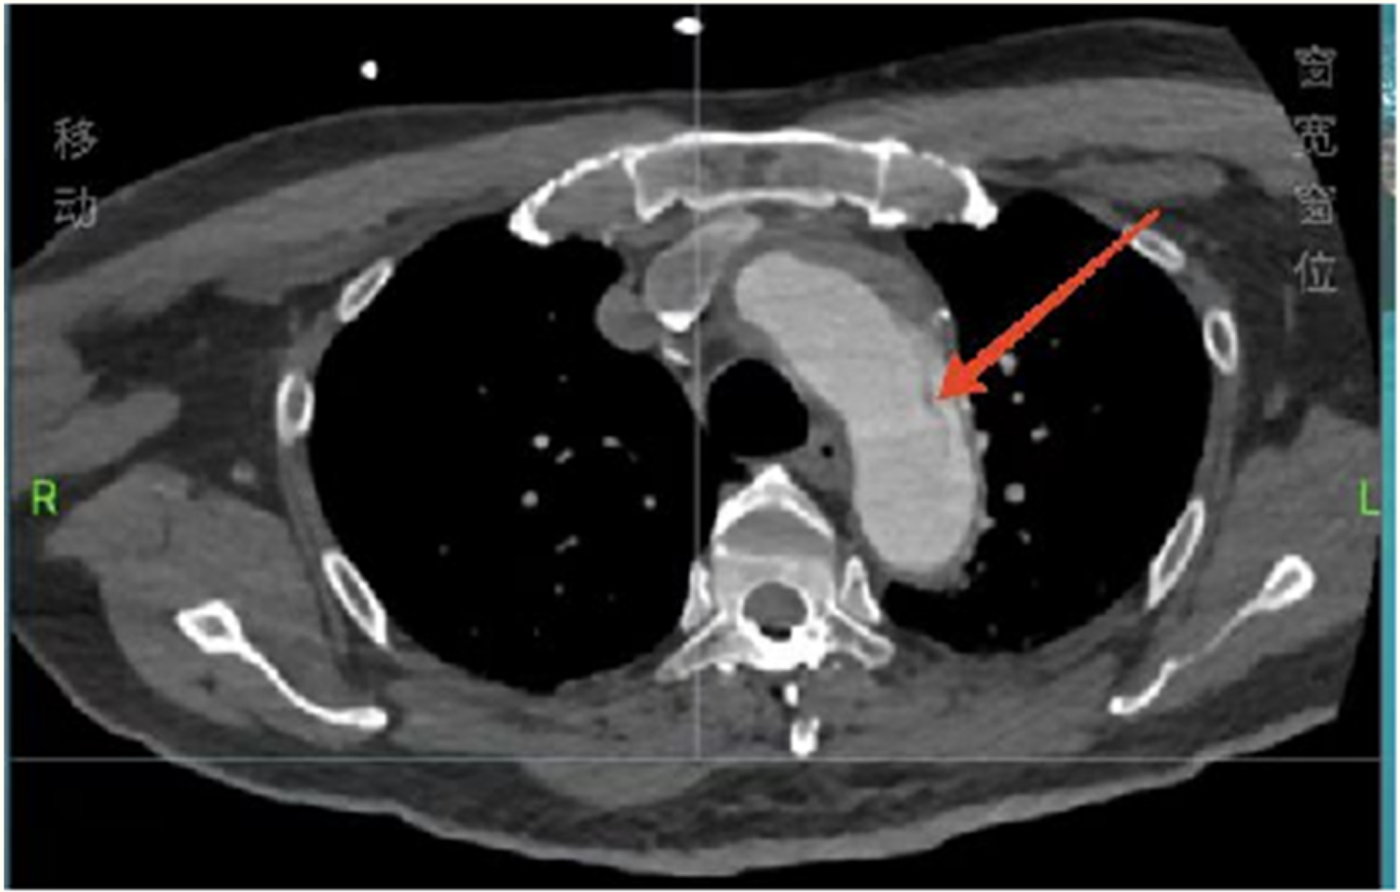

Figure 2

Total aortic computed tomography angiography showing an aortic arch dissection.

Considering the patient’s impaired consciousness and uncooperative state, endotracheal intubation and mechanical ventilation were initiated. The initial presentation of cyanosis and cold extremities suggested circulatory shock. Bedside echocardiography, along with laboratory tests, (Table 1) indicated dilation of the ascending aorta and a substantial hypoechoic pericardial effusion (Figure 1), findings highly suggestive of aortic dissection. Once stabilized on a portable ventilator, the patient underwent emergent non-contrast cranial computed tomography (CT) and whole-aortic computed tomography angiography (CTA). Imaging demonstrated hypodense shadows along the aortic arch and anterior abdominal aortic wall, confirming an aortic arch dissection with localized rupture (Figure 2). This resulted in an intramural hematoma extending into the ascending aorta, the aortic arch, and the origin of the left common carotid artery, accompanied by massive pericardial hemorrhage (Figure 3). Cranial CT revealed no abnormalities.